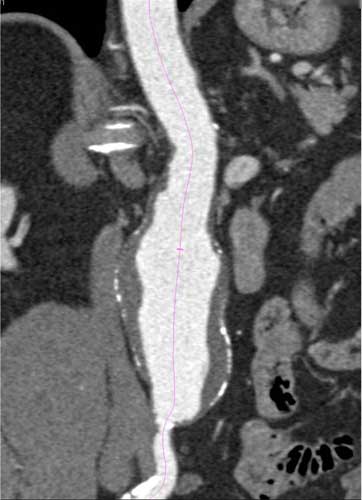

Angiotomografía computarizada mostrando una aorta abdominal agrandada o aneurisma. Para más información consulte Angiotomografía computarizada.

Nota: Las imágenes se muestra para fines ilustrativos. No trate de sacar conclusiones comparando esta imagen con otras en el sitio. Solamente los radiólogos calificados deben interpretar las imágenes.